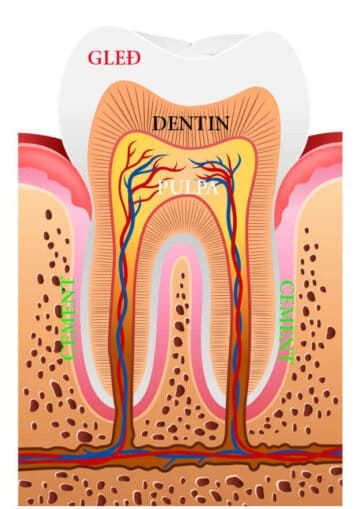

Na početku ćemo se osvrnuti na građu zuba da bismo vam lakše pojasnili ove promene.

Na površini svakog zuba nalazi se gleđ – najčvršće tkivo u ljudskom organizmu. Gleđ zuba je najčešće prozirna. Ispod nje se nalazi dentin koji je znatno mekši i žućkaste je boje. Preko dentinskih kanalića se nadražaji prenose do pulpe. Ona se nalazi u centralnom delu zuba i predstavlja organsko zubno tkivo, poznatije kao „zubni živac“, pri čemu je bitno istaći da pulpa osim nerva sadrži i krvne sudove.

Klinaste erozije zuba, kao što i sam njihov naziv govori, su promene u vidu klina koje prvo zahvataju gleđ, šire se u dentin, a nekad mogu ugroziti i vitalitet zuba šireći se ka pulpi.